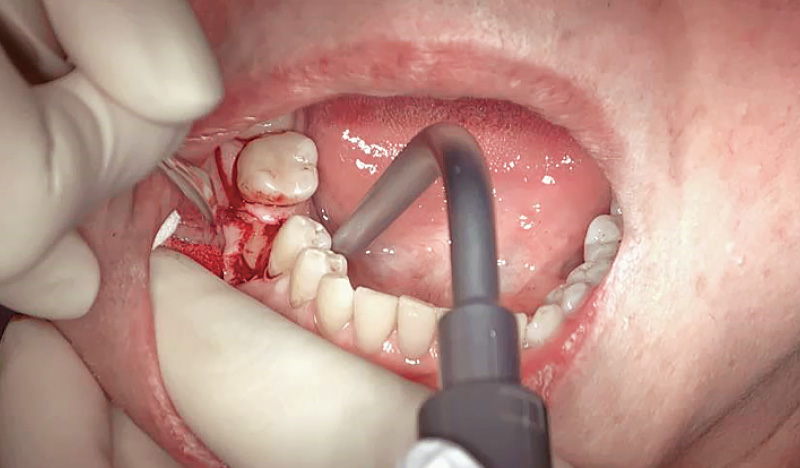

症例1-3 インプラント埋入部位の歯肉を切開。(「ル -

症例1-4 顎骨を露出させ、ドリリング後にインプラントを埋入。(「ルナビューショット」で撮影した動画より抽出) -